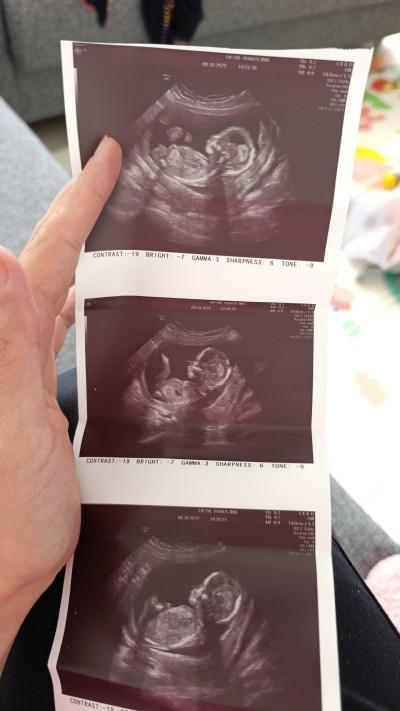

Kızlar çok rica ediyorum cinsiyet tahmini yapabilir mısınız henüz net bi şey denmedi

Nub çıkıntısına bakmaya çalıştım görüntülerden. Tam emin olamadım tabii ama kız olduğunu düşünüyorum. Gönlünüze göre olsun 😊

Sanki çıkıntısı var bana erkek gibi geldi Allah gönlünüze göre versin saglıklı sıhhatli doğmasını nasib etsin 🥰

12 haftalık misiniz banada erkek gibi geldi